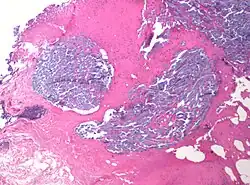

In medicine, desmoplasia is the growth of fibrous connective tissue.[1] It is also called a desmoplastic reaction to emphasize that it is secondary to an insult. Desmoplasia may occur around a neoplasm, causing dense fibrosis around the tumor,[1] or scar tissue (adhesions) within the abdomen after abdominal surgery.[1]

Desmoplasia is usually only associated with malignant neoplasms, which can evoke a fibrotic response invading healthy tissue. Invasive ductal carcinomas of the breast often have a stellate appearance caused by desmoplastic formations.

Desmoplasia refers to growth of dense connective tissue or stroma.[2] This growth is characterized by low cellularity with hyalinized or sclerotic stroma and disorganized blood vessel infiltration.[3] This growth is called a desmoplastic response and occurs as result of injury or neoplasia.[2] This response is coupled with malignancy in non-cutaneous neoplasias, and with benign or malignant tumors if associated with cutaneous pathologies.[3]